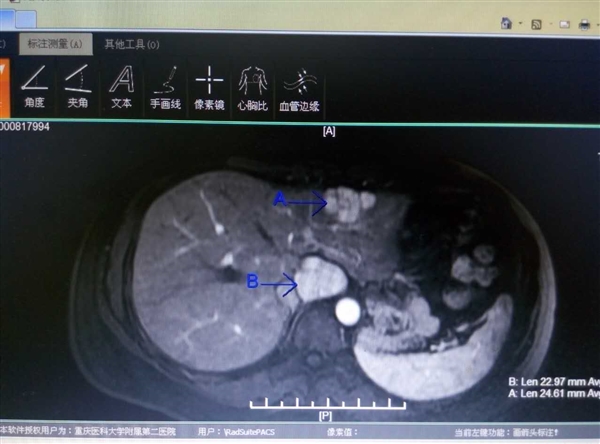

该患者为29岁的青年女性,术前的腹部B超、CT及MRI均提示左肝外叶及尾状叶占位。此前该患者已经历两次剖宫产手术。平均3年一次手术的创伤,给该患者造成了极大的手术阴影,数次有放弃手术治疗的想法。我科在龚建平主任主持下讨论认为,该患者有两处肿瘤样病变,虽诊断考虑为良性肿瘤可能性大,但肿块直径已较大(5厘米)、持续增长趋势明显,且生长部位特殊,急需手术切除。刘作金副主任表示在前期大量腹腔镜肝切除手术的基础上,该患者有机会获得腹腔镜切除机会。经充分准备,5月20日,刘作金副主任主刀,在李越副教授配合下,采用我科新引进的第三代超声刀及CUSA超吸刀等高新器械,历时2小时,顺利完成了本院首例经腹腔镜下左肝外叶联合尾状叶肿瘤切除术。